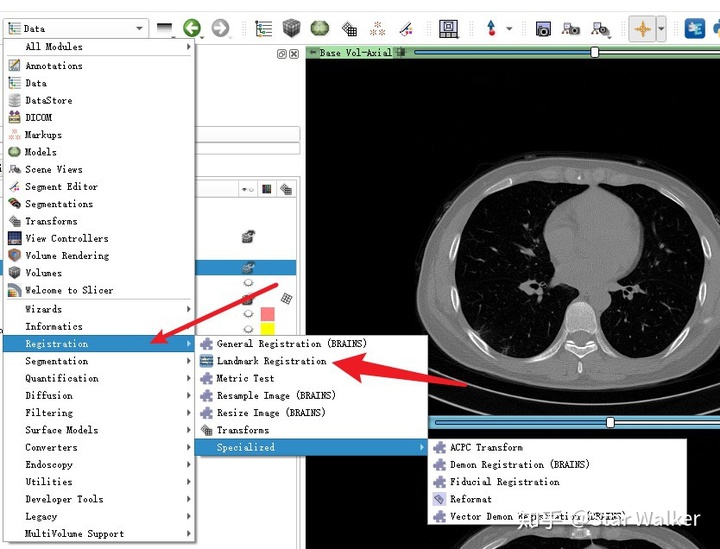

配准问题,其实属于医学图像处理中经常遇到的一类”钉子“,3D Slicer中也相应提供了多把锤子,也就是缺省集成了多种配准工具。大家可以看一眼下图。

没来的及去研究其他的配准工具,这一次基本上是上来就直接选择了Landmark Registration,拿起来就用。折腾一番,上手之后,发现这个工具还比较好用,基本能够完成预期的目标。这里的预期目标就是,可以把前后两次检查中感兴趣的局部区域,比较好的配准。这里的重点在于“局部”,也就是要配准的目标,在图像中只占很小的一部分区域。脊椎在整个人体躯干部中,所占的空间比例是很小的。这就决定了,不适合采用基于整体灰度信息的配准算法,而比较适合采用基于感兴趣区域相关的标志点对齐的配准算法。也就是通过标志点来控制哪里是感兴趣区域。这里的标志点,可以通过分割或特征点提取算法来自动生成,也可以人工直接指定生成。

启动Landmark Registration

加载好数据,改好名称之后,就可与启动Landmark Registration模块,开始配准了。启动的操作路径如下图。